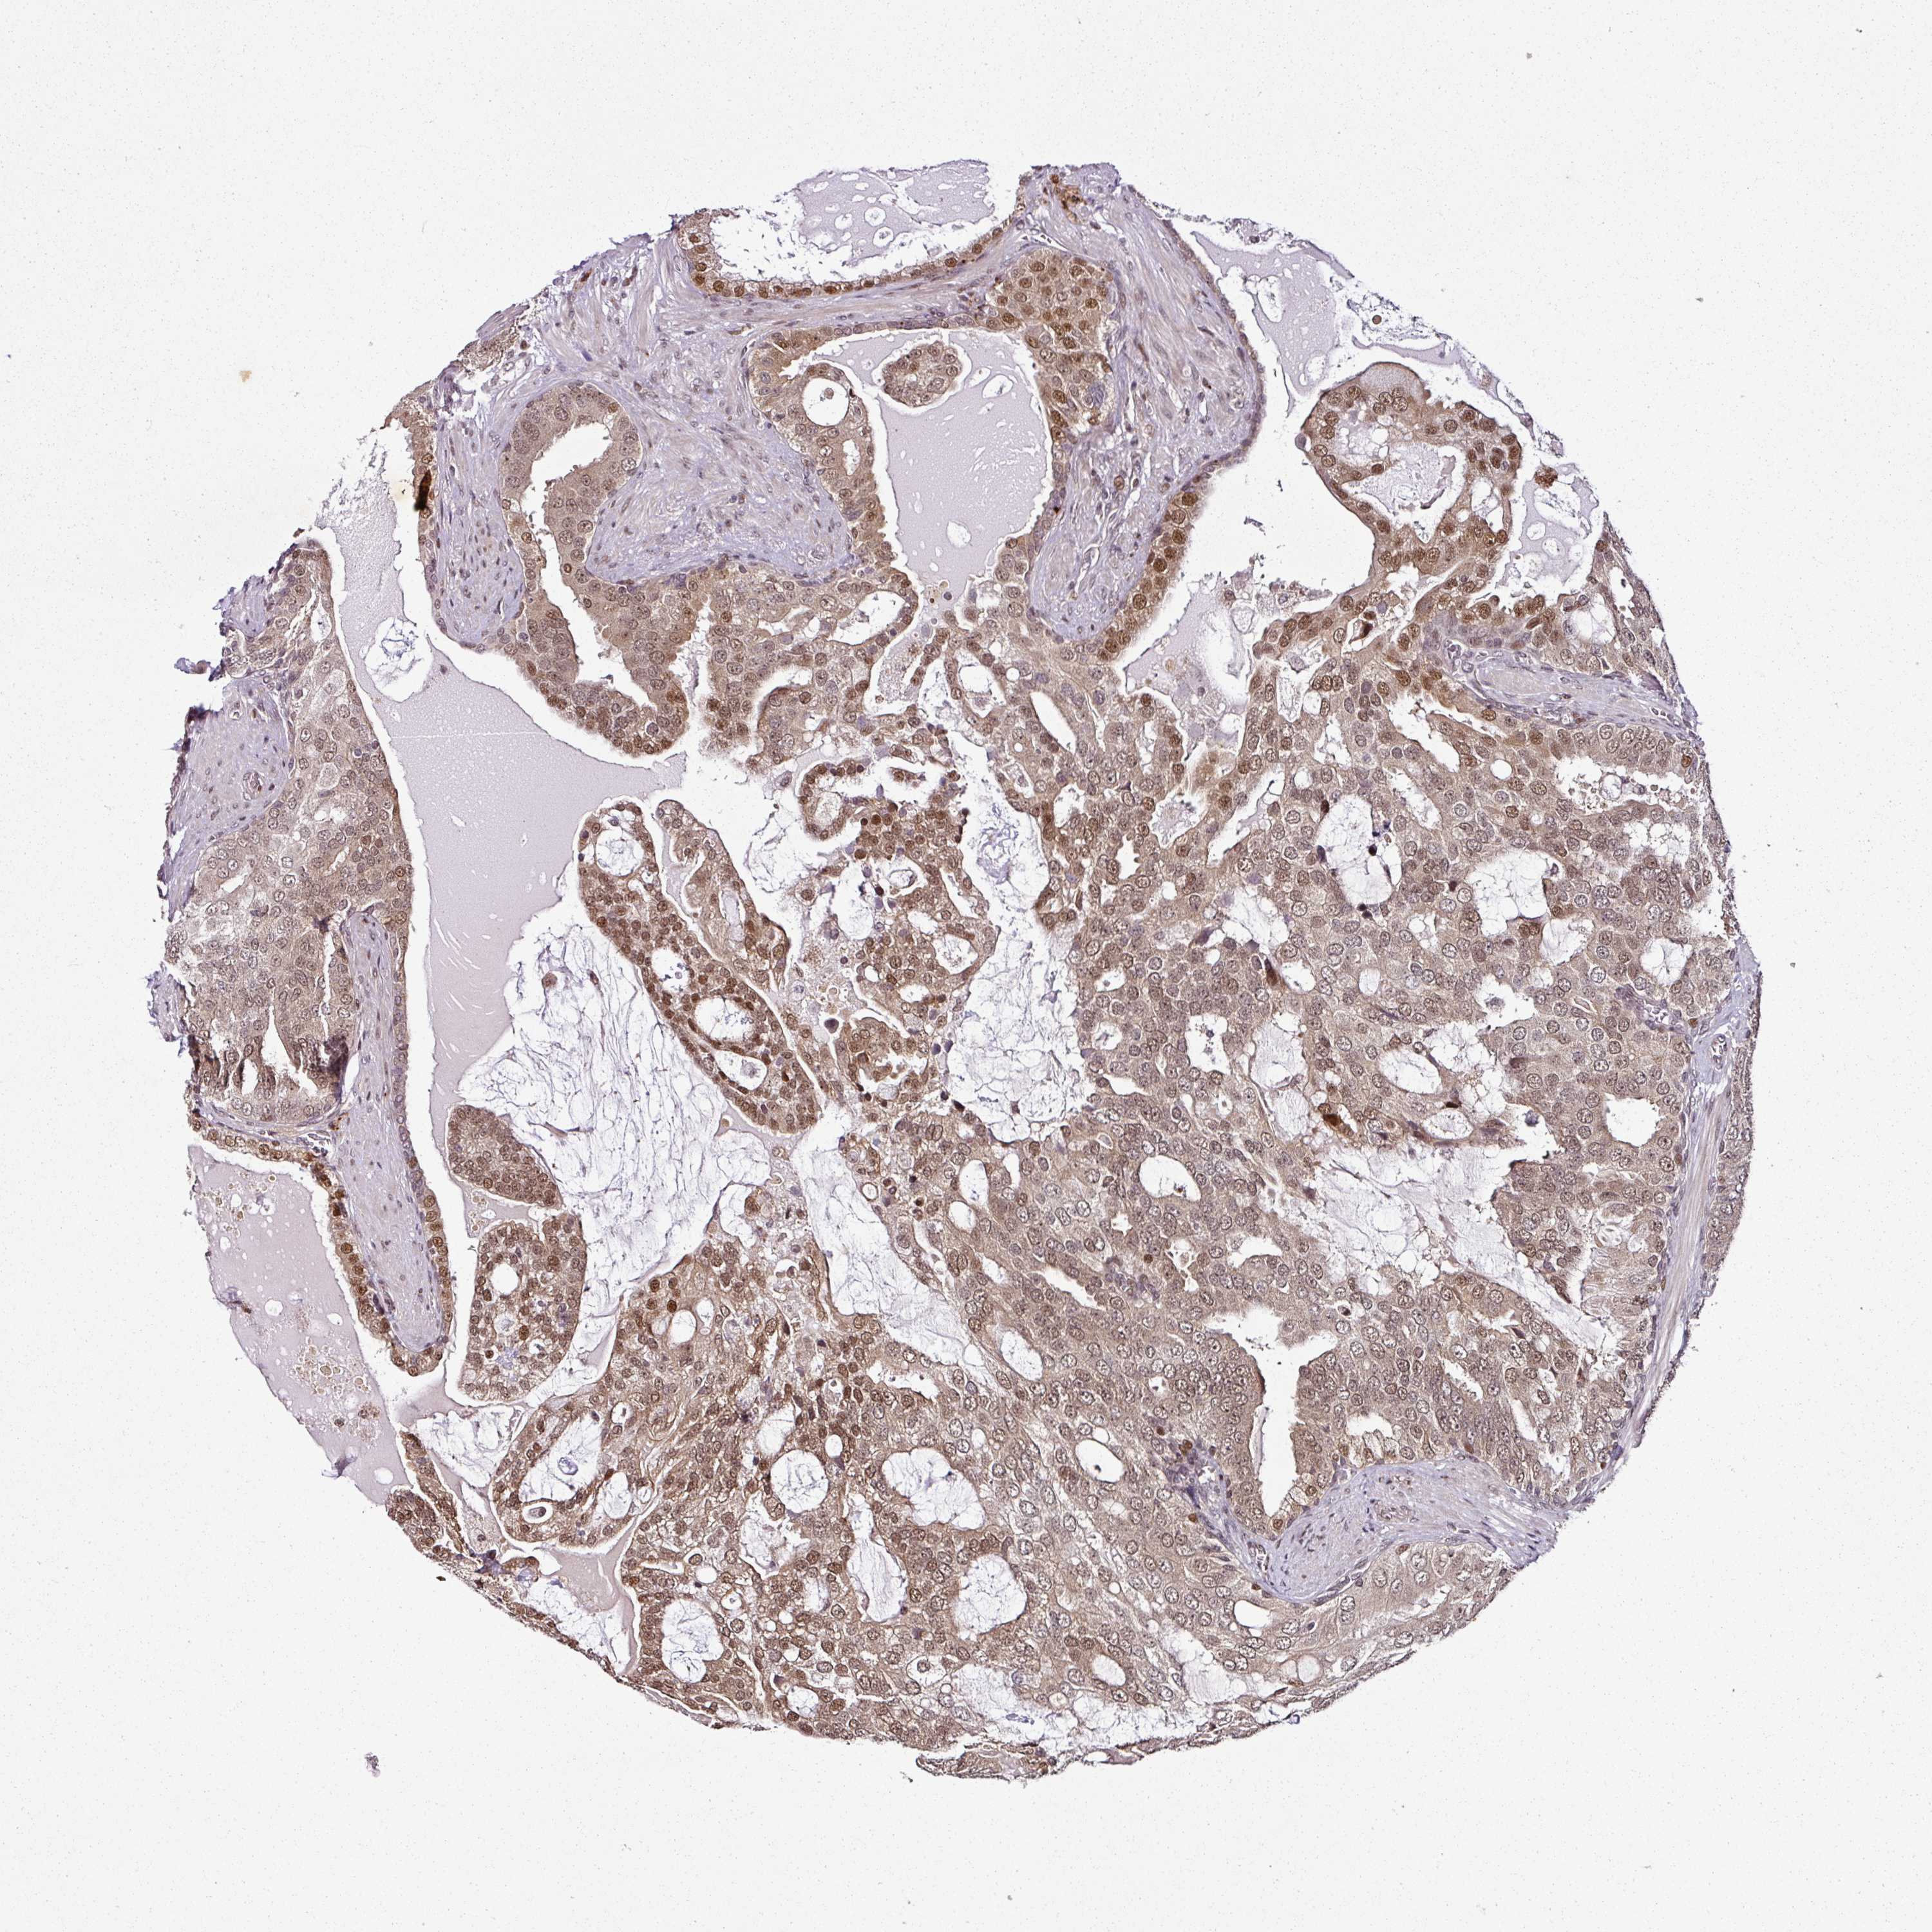

PROSTATE CANCER - Protein expressioni

A mouse-over function shows sample information and annotation data. Click on an image to view it in a full screen mode. Samples can be filtered based on level of antibody staining by selecting one or several of the following categories: high, medium, low and not detected. The assay and annotation is described here.

Note that samples used for immunohistochemistry by the Human Protein Atlas do not correspond to samples in the TCGA dataset.

Antibody stainingi

Antibody staining in the annotated cell types in the current human tissue is reported as not detected, low, medium, or high, based on conventional immunohistochemistry profiling in selected tissues. This score is based on the combination of the staining intensity and fraction of stained cells.

Each image is clickable and will lead to virtual microscopy that enables deeper exploration of all samples and also displays staining intensity scores, fraction scores and subcellular localization as well as patient and tissue information for each sample.

Antibody HPA052552

Staining

High

Medium

Low

Not detected

Intensity

Strong

Moderate

Weak

Negative

Quantity

>75%

75%-25%

<25%

None

Location

Nuclear

Cytoplasmic/membranous

Cytoplasmic/membranous,nuclear

Adenocarcinoma, High grade

Adenocarcinoma, Low grade